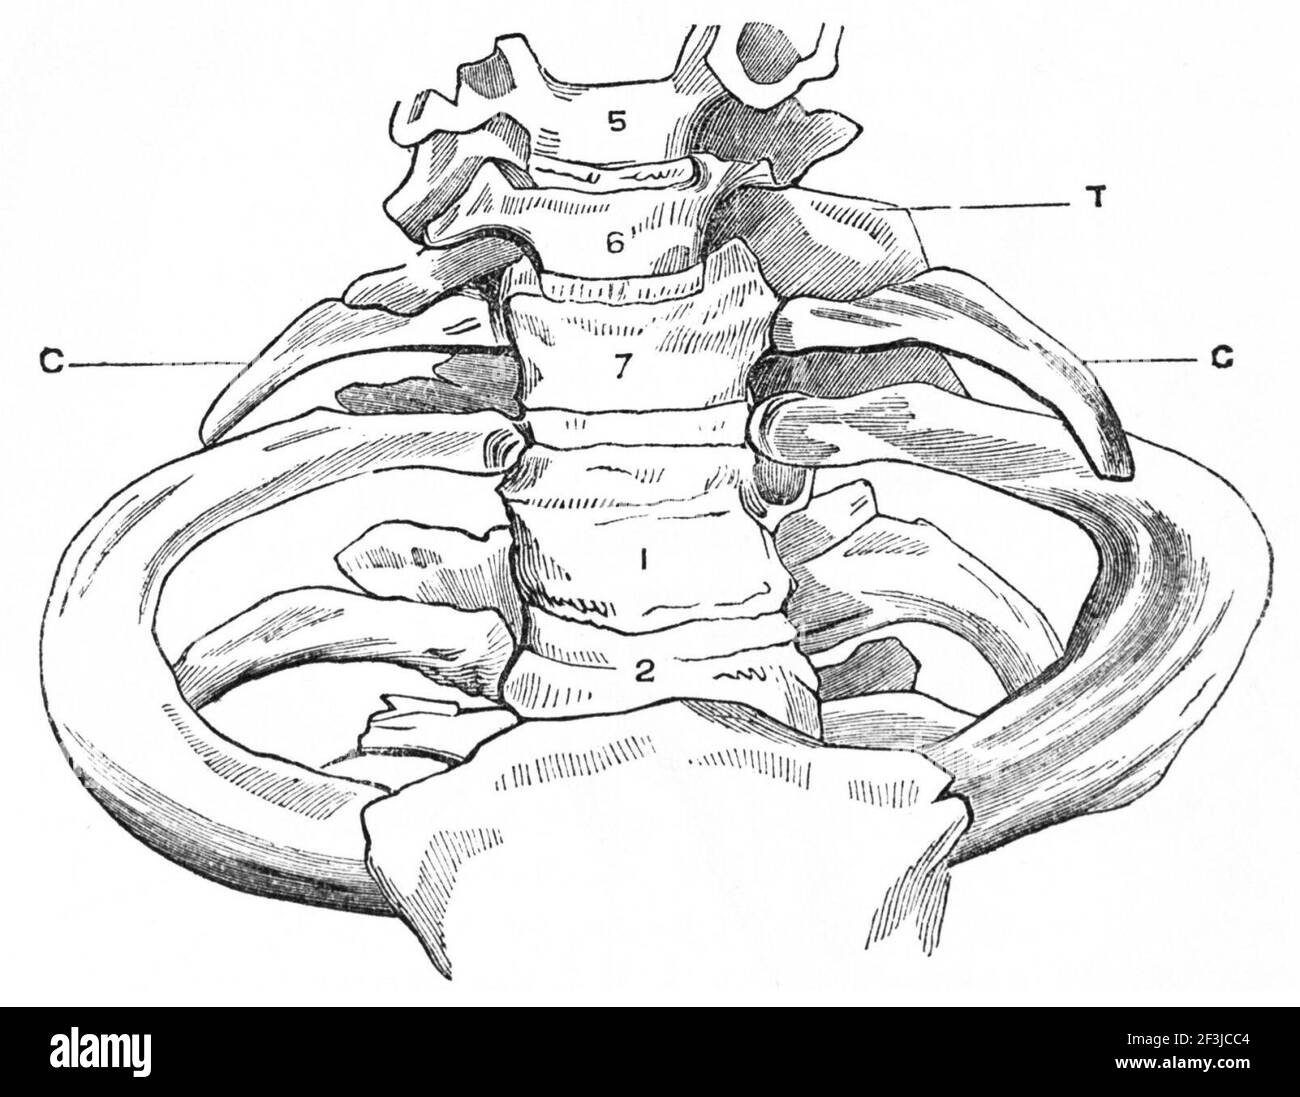

RMJ4C3NM–Questo diagramma di PSM V25 D742 illustra la struttura anatomica delle costole cervicali e il processo trasversale delle vertebre cervicali. È una rappresentazione dettagliata utilizzata nello studio dell'anatomia umana, concentrandosi sulla struttura vertebrale e sullo sviluppo delle costole.

RMPFM8F8–Una guida completa all'anatomia e alla fisiologia, che descrive dettagliatamente la struttura del torace e le variazioni nella formazione delle costole, comprese le costole sovrannumerarie e la presenza di processi trasversali. Il lavoro esplora l'analogia tra processi trasversali e costole, evidenziando le variazioni anatomiche negli esseri umani e negli animali.

RMMA77DE–. Elementari di anatomia e fisiologia : Per college, accademie e altre scuole . Una vista anteriore dei legamenti delle vertebre e delle costole. 1, la sezione anteriore del legamento vertebrale. 2, il costo anteriore- legamento vertebrale. 3, l'interno legamento trasversale. 4, il Inter-Ar- o sovracapacità per particolari legamento, colleganti la testa della costola al sub intervertebrale- posizione. Una vista dell'articolazione della mandibola, dato dalla segatura attraverso il giunto. 1, la Fossa glenoide. 2, il tubercolo per condilo nel suo avanzamento- zioni. 3, la cartilagine Inter-Articular. 4, il superiore della cavità sinoviali. 5, il file INF